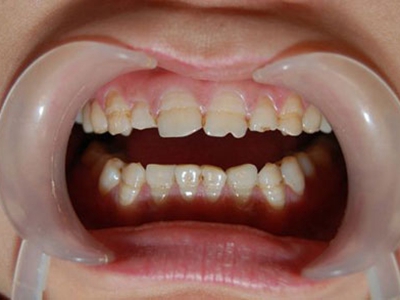

牙釉质发育不全牙齿表面有白斑和横沟图

牙釉质发育不全患者,其牙齿整体可呈灰黄色,表面出现白斑及横沟样的凹陷,由于致病因素出现在牙发育期,故受累牙往往呈对称性。